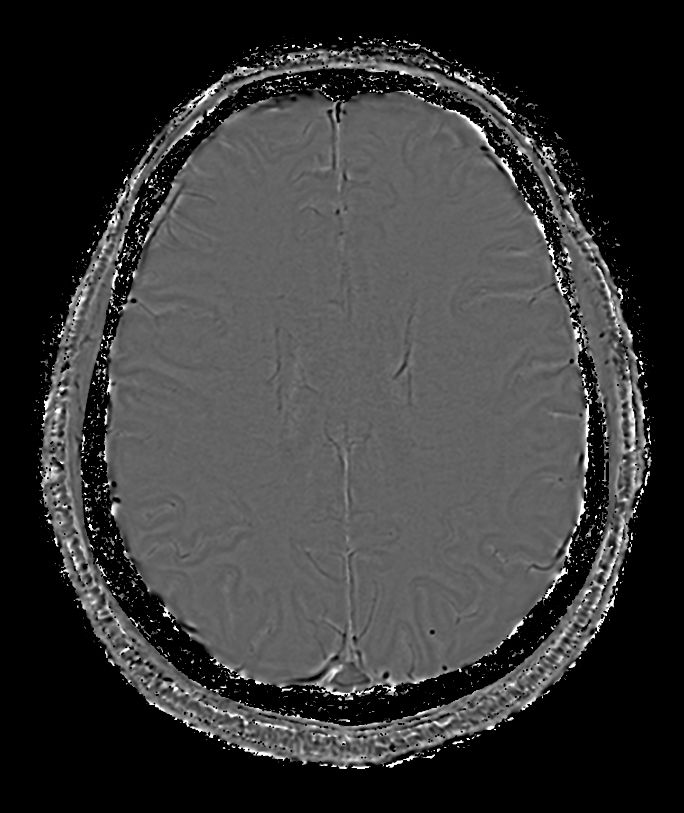

SWIp (minIP) Compressed SENSE

-

SWIp (Phase) Compressed SENSE